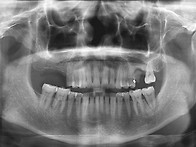

발치 즉시 임플란트

임플과 이소연 10.04.082007년 처음병원에 오셨을 때의 사진과 x-ray입니다. 위의 양쪽어금..